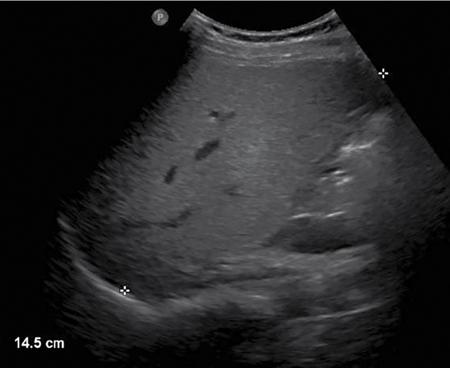

Ritu K. Kashikar, Shrinivas B. Desai Imaging is the mainstay of noninvasive diagnosis of the spectrum of abdominal pathologies or proving absence off thereof. Knowledge of normal anatomy and important normal variants is thus essential for the radiologist in order to avoid misinterpretation or erroneous diagnosis. This chapter highlights the normal anatomy of the hepatobiliary systems including the blood vessel and draining ducts and discusses relevant anatomical variants which may have important clinic implications. The liver is the largest abdominal organ, occupying the right upper abdominal quadrant and is in close approximation with the diaphragm, stomach and the gallbladder. It is largely covered by the costal cartilages. The liver is encapsulated by Glisson’s capsule which is a dense layer of connective tissue. It is covered by peritoneum, except in the regions of gallbladder fossa, fossa for inferior vena cava (IVC), and the bare area. The bare area is the posterocranial aspect of the liver, adjacent to the dorsal body wall, which is not covered by peritoneum. The liver has two surfaces, the convex diaphragmatic surface and a concave visceral surface. The slit in the hepatic hilum is called the porta hepatis and is penetrated by the right and left hepatic ducts (LHDs), hepatic artery and portal vein (PV). The distal portion of the lesser omentum is called the hepatoduodenal ligament and contains the common bile duct (CBD), hepatic artery, PV, nerves of liver and lymphatics. The liver has dual blood supply with hepatic artery providing 25% of hepatic blood and rest by portal vein (Fig. 9.2.1). Five ligaments connect the liver to the undersurface of the diaphragm. These include the falciform, the coronary and two lateral ligaments, all of which are peritoneal folds. The fifth ligament is a fibrous cord-like structure and represents the obliterated umbilical vein. The peritoneum invaginates into the liver parenchyma leading to formation of fissures. There are four normal fissures: fissures for the ligamentum teres, ligamentum venosum and gallbladder and the transverse fissure (Fig. 9.2.2). The liver is organized into microscopic functional units called lobules or acini. A central terminal hepatic venule surrounded by four to six terminal portal triads form a polygonal unit called the hepatic lobule. The terminal portal triad branches line the periphery of the unit. Between the terminal portal triads and the central hepatic venule the hepatocytes are arranged in one cell thick plates, surrounded by sinusoids. The blood flows from the terminal portal triad through sinusoids into terminal hepatic venule. Bile formed within the hepatocytes empties into terminal canaliculi which coalesce into the bile ducts (Fig. 9.2.3). This structure of the functional hepatic unit forms the basis of various functions of the liver. The normal relations of the liver are: The liver can be divided into right, left and caudate lobes. The right and left lobes are separated by the interlobular fissure and is oriented along a line passing through the gallbladder fossa inferiorly and the middle hepatic vein (MHV) superiorly (Fig. 9.2.4). This plane runs from the left of the IVC to the left of the gallbladder fossa and is a called the Cantlie’s line. Use of standardized, segmental anatomy is imperative because it facilitates communication and treatment planning. The segmental anatomy of liver is primarily based on vascular anatomy. The right lobe is divided into anterior and posterior sectors by of the right hepatic vein (RHV). The left lobe is divided into medial and lateraI sectors by an oblique plane connecting the left hepatic vein (LHV) and the falciform ligament. The liver is divided into upper and lower segments at the level of main portal vein (MPV) bifurcation (Fig. 9.2.5). Various systems are used in classification of liver anatomy. These are discussed in Table 9.2.1. The Couinaud’s system is the most commonly used and divides eight sections/segments which are discussed in details below (Table 9.2.2). 1. Segment 1 – Caudate lobe Bounded anteriorly and medially by the fissure for ligamentum venosum (Fig. 9.2.6). 2. Segment 2: Superior segment of the left lateral sector/section Bounded medially by falciform ligament and inferiorly by plane of MPV, also known as the posterior lateral sector (Bismuth, FCAT) (Fig. 9.2.7). 3. Segment 3: Inferior segment of left lateral sector/section Bounded medially by the falciform ligament and superiorly by the plane of the MPV bifurcation, also referred to as lateral anterior sector (Bismuth, FCAT) (Fig. 9.2.8). 4. Segment 4: Left medial sector/section Bounded laterally by falciform ligament and medially by Cantlie’s line (Fig. 9.2.9). 5. Segment 5: Inferior segment of the right anterior sector/section Bounded anteriorly by the gallbladder fossa and posteriorly by the plane of the RHV, superiorly bounded by the plane of MPV bifurcation (Fig. 9.2.10). 6. Segment 6: Inferior segment of the right posterior sector/section Bounded anteriorly by plane of the RHP and superiorly by the plane of the MPV bifurcation (Fig. 9.2.11). 7. Segment 7: Superior segment of the right posterior sector/section Bounded anteriorly by the plane of the RHV and inferiorly by the plane of the MPV bifurcation (Fig. 9.2.12). 8. Segment 8: Superior segment of the right anterior sector/section Bounded anteriorly by the plane of the gallbladder fossa and MHV, posteriorly bounded by the plane of the RHV and inferiorly by the plane of the MPV bifurcation (Fig. 9.2.13). Owing to its broad area of contact with the anterior abdominal wall, the liver is an ideal organ for evaluation with sonography. Ultrasound is commonly used for evaluation of size of the liver. On longitudinal scans obtained through the midhepatic line, if the liver measures 13 cm or less, it is normal in 93% of individuals (Fig. 9.2.14). The size of liver in various planes is discussed in chapter on normograms. When the area of contact between the liver and the anterior border of the right kidney, exceeds below two thirds of the kidney, the liver is considered as enlarged. The normal liver is homogeneous with fine echoes and appears evenly bright. The hepatic veins, PV and fissures interrupt the homogeneity of the liver parenchyma (Fig. 9.2.15). The parenchymal echogenicity may vary depending on the equipment, transducer and gain settings and should be judged by comparison with internal references like right renal cortex, body of the pancreas and PV walls. When compared with the adjacent normal right renal cortex the liver normally appears hyperechoic or isoechoic. The pancreas in a young individual is hypoechoic compared to the liver, and isoechoic in middle aged adults. As age progresses and fatty infiltration of the pancreas occurs, the pancreas appears hyperechoic to the liver. The liver is hypoechoic to the spleen. The normal liver reveals a density of 55–65 HU on nonenhanced scan and should appear homogenous with the exception of hypodensity in the regions of vessels and fissures. The liver parenchymal enhancement is minimal the arterial phase, with increase in density by only approximately 10 HU. This phase is usually to access vascular anatomy and to detect neovascular enhancing lesion like HCC, metastasis. Considering the fact that 75% of heptic venous supply is from the PV, the normal hepatic parenchyma shows maximum enhancement in the portal venous phase. During the venous/delayed phase the hepatic attenuation starts falling (Fig. 9.2.16). The hepatic fissures appear as linear fat containing structures. All the four fissures are well identifies on CT (Figs. 9.2.17–9.2.20). Normal liver should demonstrate uniform T1 signal similar or isointense to the paraspinal muscles and slightly hyper intense to the spleen. No signal drop should be seen on in or opposite phase. On T2W1 images liver appears slightly hyperintense to paraspinal muscles, isointense to pancreas and hypointense to spleen (Fig. 9.2.21). Following administration of extracellular contrast agents the normal liver parenchyma enhances on PV phase similar to that seen on CT. The arterial phase is preserved to determining vascular anatomy, variants and tumoural enhancement. Gadoxetic acid (Eovist) and gadobenate dimeglumine (MultiHance) are hepatobiliary agents showing excretion by the liver. In the case of gadoxetic acid, hepatic excretion is ~50%, which allows imaging in the hepatobiliary phase at ~20 minutes following injection. Gadobenate has only 3%–5% biliary excretion with hepatobiliary phase at approximately 40 minutes (Fig. 9.2.22). This property makes these agents useful in detection of nonhepatocyte containing lesions which appear hypointense to background liver on hepatobiliary phase. Hepatic anatomic variants are relatively common and represent normal interindividual variation of liver morphology. Normal Anatomic Variants Anatomic anomalies Accessory and pseudofissures may be seen in the liver. True accessory fissures result from infolding of the peritoneum usually along the undersurface of the liver and are rare. The inferior accessory fissure is the commonest accessory fissure and divides the posterior segment of the right hepatic lobe into lateral and medial portions. Diaphragmatic slips may cause indentation over the liver surface and are not commonly seen on imaging (Fig. 9.2.23). Leftward extension of the lateral segment of the left hepatic lobe appearing as a crescentic density that wraps around the spleen is referred to as sliver of liver. The left lobe of the liver may exhibit various forms: leaf like; spatular; truncated pyramid/wedge shaped; and a bifid appearance (Fig. 9.2.24). Elongated left lobe may be mimic splenomegaly, perisplenic hypoechoic collections or less commonly tumours. Imaging clues to diagnosis are establishing contiguity with liver and visualization of parenchymal vessels coursing through. The portion of the liver that extends medially from the right lobe between the IVC and fissure for ligamentum venosum is called the caudate lobe. The caudate lobe is divided inferiorly into a lateral caudate process and a medial papillary process. The medial papillary process projects medially towards the pancreatic head and has applied importance (Fig. 9.2.25). Riedel’s lobe is a tongue-like projection from the anterior aspect of the right lobe and the most common accessory lobe of the liver. It is seen most frequently in asthenic women. The reported prevalence of RL, ranges from 3.3% to 14.5% and the prevalence is higher in women than in men. It can be 20 cm or more in length and may extend up to the iliac fossa. It is usually asymptomatic and is discovered incidentally (Fig. 9.2.26). Accessory liver lobes are defined as a supernumerary lobe of normal hepatic parenchyma in continuity with the liver. This is a rare entity and usually occurs as a result of congenital ectopic hepatic tissue, although rarely may occur as a result of trauma or surgery. Various systems are proposed for classification of ALL. Another method of classification has been proposed based on biliary drainage and presence or absence of capsule. Accessory lobes can be readily diagnosed and characterized on CT or magnetic resonance imaging (MRI) done for related or unrelated conditions. CT shows the lesion as a soft–tissue density mass attached to the liver and isodense to the organ. The portal/hepatic venous branches can be seen coursing through it, in contiguity with the liver (Fig. 9.2.27). The coeliac axis trifurcates into common hepatic, splenic and left gastric arteries at the level of T12–L1. The common hepatic artery becomes the proper hepatic artery after origin of the gastro-duodenal artery. The hepatic artery proper ascends anterior to the PV and medial to the CBD and divides in to right and left hepatic artery (LHA). Occasionally the middle hepatic (segment 4) artery arises from hepatic artery proper. The hepatic artery appears as a tubular hypoechoic structure and shows antegrade flow on Doppler (Fig. 9.2.28). Normally the resistive index is low ranging between 0.55 and 0.7. The hepatic artery, its anatomy, branches, course, calibre are best evaluated on arterial phase of dynamic CT (Fig. 9.2.29). This is also the preferred modality prior to hepatobiliary surgical planning. Contrast-enhanced MRI also shows the above details but spatial resolution is lower. Road map of the arterial vascularity of the donor and recipient is a prerequisite for transplant surgery and complex hepatobiliary surgery. Detailed hepatic arterial anatomy and its variations have its significance in liver surgeries and interventional hepatic procedures, relative to the hepatic lobe involved. A classification method was described by Michel et al. in 1955, and is discussed in Table 9.2.3 (Fig. 9.2.30). I: standard anatomy ~60% (range 55%–61%) II: replaced LHA ∼7.5% (range 3%–10%) III: replaced RHA ~10% (range 8%–11 %) IV: replaced RHA and LHA ~1% V: accessory LHA from LGA ~10% (range 8%–11%) VI: accessory RHA from SMA ~5% (range 1.5%–7%) VII: accessory RHA and LHA ~1% VIII: accessory RHA and LHA and replaced LHA or RHA ~2.5% IX: CHA replaced to SMA ~3% (range 2%–4.5%) X: CHA replaced to LGA ~0.5% Other unclassified variants are: The two most common variants are the replaced right hepatic artery (RHA) arising from the SMA (Fig. 9.2.31) and replaced LHA arising from the left gastric artery (Figs. 9.2.32–9.2.34). Segment 4 artery – Middle hepatic artery (MHA) The middle hepatic artery usually arises from the LHA, it may, however, arise from the RHA (Fig. 9.2.35). The knowledge regarding origin of MHA is imperative in transplant surgery. The MHA can arise from RHA in Patients with replaced LHA. In patients with replaced RHA, the MHA arises from LHA (Fig. 9.2.36). Because of the considerable variability of hepatic arterial anatomy, assessment of this anatomy is crucial in the preoperative evaluation of potential living liver donors. Relevance of donor and recipient arterial anatomy is discussed in details in chapter on liver transplant. The relationship between the arterial variant and tumour is important to establish prior to major surgeries. Injuries to aberrant hepatic vessels and secondary ischaemic biliary strictures can be avoided. A replaced RHA has a more posterior course and long length. This variant may be advantageous in patients undergoing right lobar resection. However, there is greater propensity of involvement of replaced RHA by pancreatic head. The radiologist must be vigilant in reporting this variant (Fig. 9.2.37). Accessory RHA can, however, be sacrificed even if encased by neoplasm. An accessory LHA needs to be ligated separately in surgeries where blood supply in the porta hepatis is occluded. Replaced LHA from LGA maybe injured in case of surgeries at the level of hiatus. Hence this variant should be informed to surgeon in patients undergoing gastric surgeries. Preoperative mapping of the hepatic arterial anatomy prior to placement of intraarterial chemotherapy pumps is essential because it helps in deciding whether the candidate is suitable for the procedure and also if technical modifications are needed. The intraarterial infusion pump should be placed in the dominant hepatic artery as proximal as possible, but beyond GDA origin. Inpatients with standard anatomy, the pump is usually placed in the hepatic artery prior just after GDA origin. The location of pump can be modified in patients with variant anatomy, based on origin of GDA and dominant hepatic vessel. The PV is the main vessel in the portal venous system and drains blood from the gastrointestinal tract and spleen to the liver.